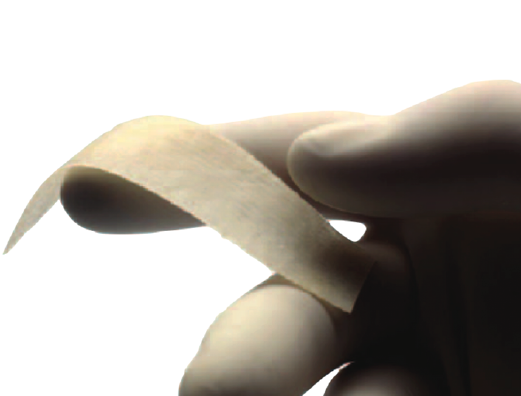

Figura 4. EpiFlex®. Matriz de colágeno acelular humano.

La técnica realizada en nuestros casos fue la resección del puente calcaneoastragalino y la interposición de matriz dérmica de colágeno humano acelular, de marca EpiFlex®(Figura 4), reducción del pie plano valgo y artrorrisis mediante endoprótesis de tipo PitStop®(Figura 5).